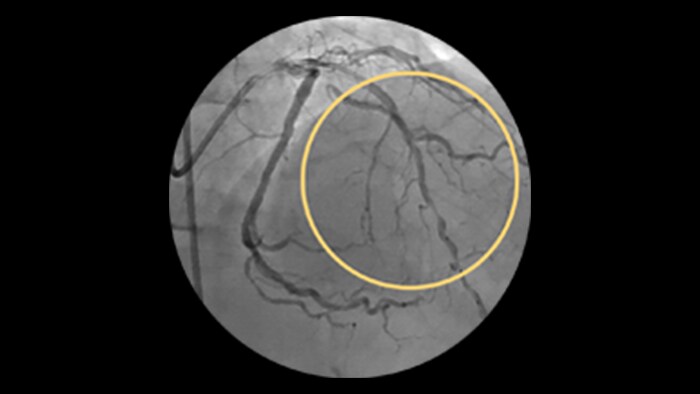

SVG patency rates have been reported at approximately 80% at 1 year and approximately 50% at 15 years and beyond.1